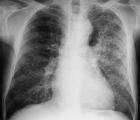

肺炎1、主要引起人類大葉性肺炎:

(1)、成人75%的肺炎鏈球菌肺炎及50%以上嚴重的肺炎鏈球菌菌血症是由1—8型、12、14及16型肺炎鏈球菌引起,以1、2、3型最多見,其中3型肺炎鏈球菌因產生大量莢膜,毒力強,病死率高。

(2)、兒童大葉性肺炎以1、6、14和19型多見,其中以14型最常見。

該菌常寄居在正常人口腔及鼻咽部,一般不致病,只形成帶菌狀態。但當機體免疫力下降時可致病。臨床症狀為突然發病,高熱、寒戰、胸膜劇烈疼痛、咳鐵鏽色痰。10%—20%的患者可於高熱期伴發菌血症。其病理表現主要是最初肺泡內有大量纖維蛋白滲出液,繼之是紅細胞和白細胞向肺泡內滲出,最終導致病變部位肺組織實變。病變通常僅累及單個肺葉,故稱為大葉性肺炎。肺炎鏈球菌也可侵入機體其他部位,引起胸膜炎、中耳炎、乳突炎、心內膜炎及化膿性腦膜炎等,尤其是呼吸道病毒感染者或嬰幼兒、老年體弱者。